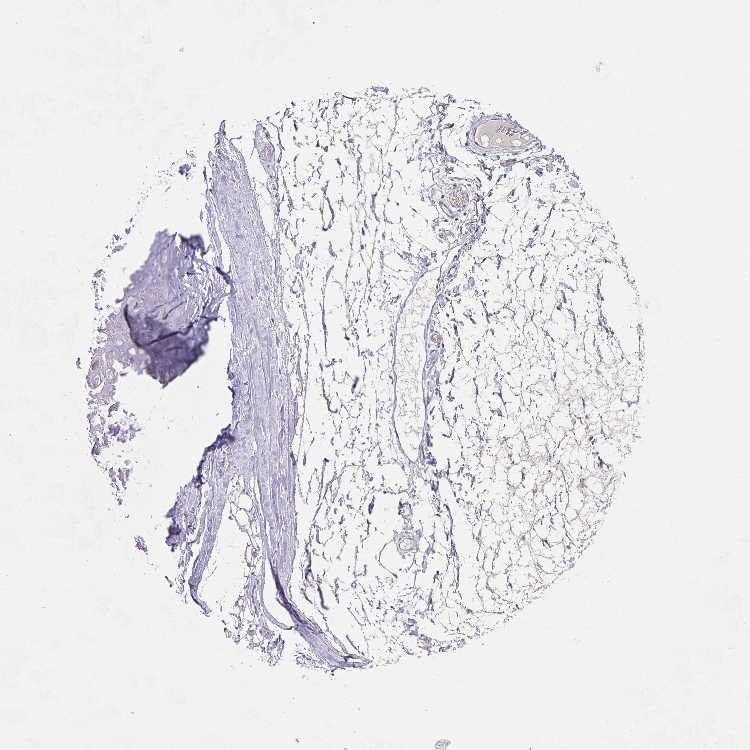

SOFT TISSUE 1 - Antibody stainingi

Antibody staining in the annotated cell types in the current human tissue is reported as not detected, low, medium, or high, based on conventional immunohistochemistry profiling in selected tissues. This score is based on the combination of the staining intensity and fraction of stained cells.

Each image is clickable and will lead to virtual microscopy that enables deeper exploration of all samples and also displays staining intensity scores, fraction scores and subcellular localization as well as patient and tissue information for each sample.

Antibody HPA034771

Chondrocytes Not detected

Fibroblasts Not detected

Peripheral nerve Not detected

SOFT TISSUE 2 - Antibody stainingi